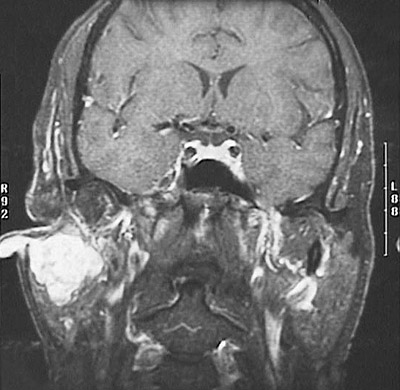

This coronal MRI scan of the head demonstrates a

pleomorphic adenoma

, or mixed tumor, arising in the right parotid gland.